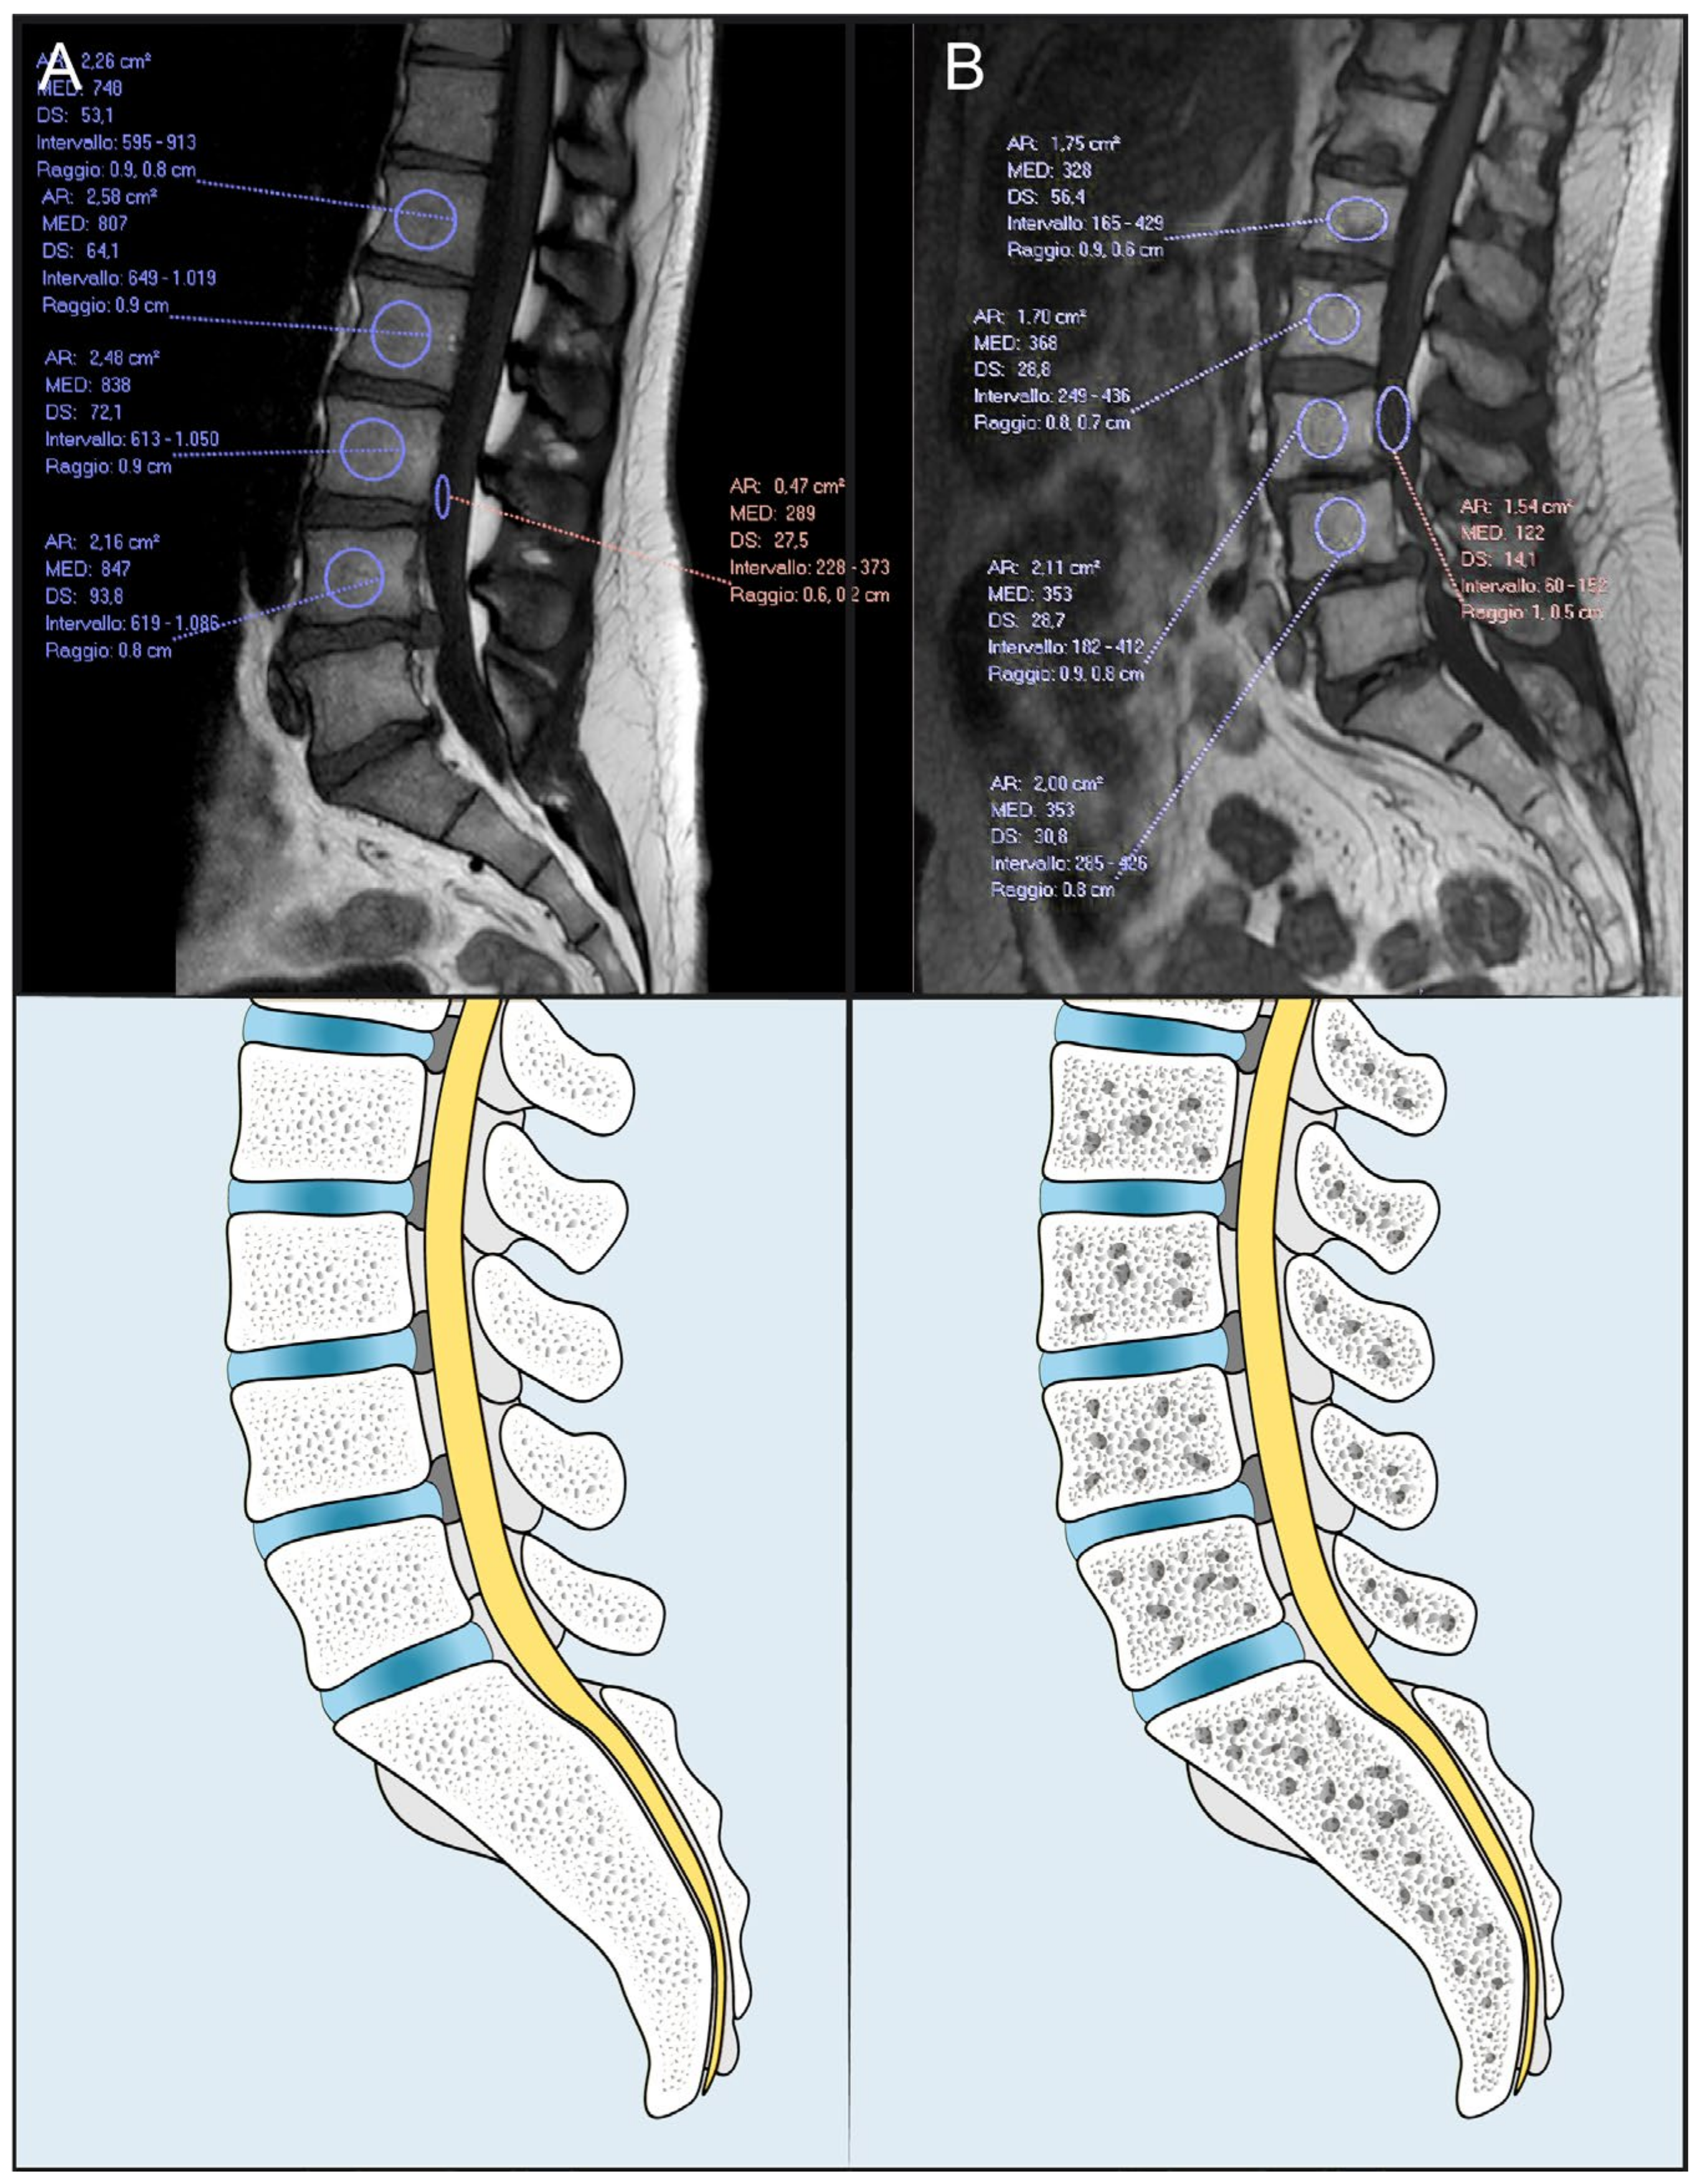

3.3. High vs. Low M-Score Patients

3.4. Infectious Status

3.5. Mechanical Complications